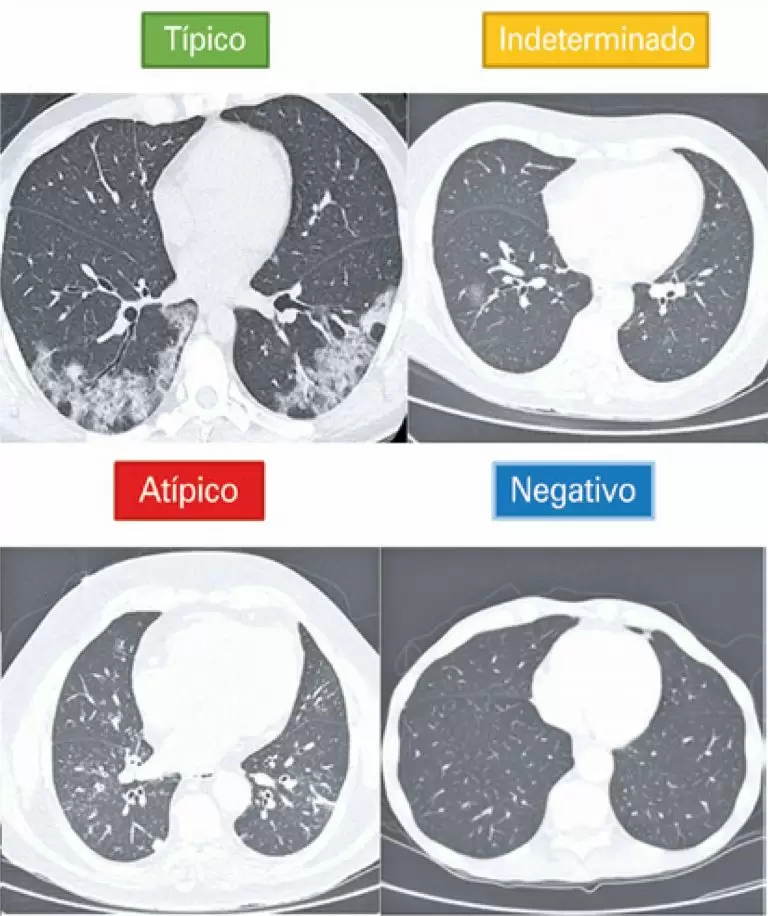

Estudo retrospectivo de centro único que avaliou 39 pacientes com RT-PCR negativa para COVID-19, submetidos à tomografia computadorizada de tórax e que tiveram diagnóstico final clínico ou serológico de COVID-19. A classificação tomográfica visual foi avaliada de acordo com o Consenso da Radiological Society of North America e o software desenvolvido com inteligência artificial para detecção automática de achados e estimativa de probabilidade de COVID-19.

Na análise tomográfica visual, somente um deles (3%) apresentou tomografia computadorizada classificada como tendo resultado negativo, 69% foram classificados como típicos e 28% como indeterminados. Na avaliação com uso de software, somente quatro (cerca de 10%) tiveram probabilidade de COVID-19 <25%.